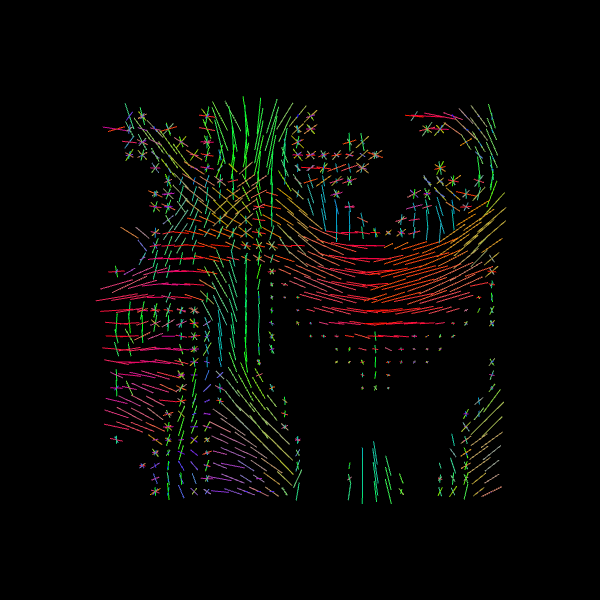

For quality assurance, we can visualize an axial slice from the direction field estimated by the CSA model. Each glyph represents a local fiber orientation derived from the ODF peaks. The underlying ODFs are not shown here.

scene = window.Scene()

scene.add(

actor.peak_slicer(

csa_peaks.peak_dirs[20:50, 55:85, 37:38], peaks_values=csa_peaks.peak_values[20:50, 55:85, 37:38], colors=None

)

window.record(scene=scene, out_path="csa_direction_field.png", size=(600, 600))

Image("csa_direction_field.png")

../_images/e401dd1b6d94fe4f2384165b5fef0c0fe2717a93e33004cc0ced94709a527f2c.png